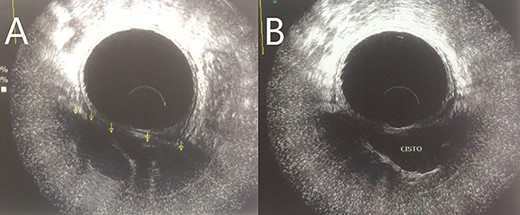

A 28-year-old female patient with a surgical history of excision of a pilonidal cyst 2 years ago presented with local discomfort when sitting for 6 months. The examinations performed suggested a tailgut cyst, and the principal differential diagnosis was a recurrence of the pilonidal cyst. Abdominal and pelvic MRI identified an extensive collection occupying soft tissues in the sacrococcygeal region, extending anteriorly under the sacrum and coccyx to the retrorectal space on a closed end, apparently without continuity with the subcutaneous mesh in the buttocks region. It had thin and regular walls and partial parietal enhancing of the rectosacrococcygeal portion, measuring 9.9 × 7.9 × 3.9 cm, with an estimated volume of 158 ml. The collection exerted a modest compressive effect on an adjacent posterior rectal wall but maintained a well-defined cleavage plane (Fig. 1). Colonoscopy showed extrinsic compression in the posterior and right lateral wall of the inferior rectum, above the puborectalis muscle (Fig. 2). Rectal ultrasonography showed multicystic content in the retrorectal space (Fig. 3). The patient underwent a complete resection of the tailgut cyst via posterior intergluteal access. She was discharged on the first postoperative day, with no complications or sequelae and no evidence of recurrence until 18 months of postoperative follow-up.

Transabdominal USG shows multicystic lesions in the retrorectal space. Transrectal USG provides information on the nature of the retrorectal mass, such as solid versus cystic, extension and degree of invasion of the rectal wall, if any [2, 9].